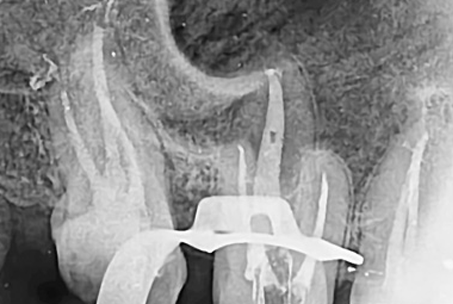

위 사진들은 현직 치과의사들이

저희 웃는얼굴 치과에서 치료 받은 실제 사례들입니다.

비 전문가 눈에는 그냥 흔한 엑스레이 사진일 뿐이겠지만

치과의사들이라면 알아챕니다.

저 치료가 얼마나 난이도 있는 치료였는지,

얼마나 정성이 들어갔는지를 말이지요.